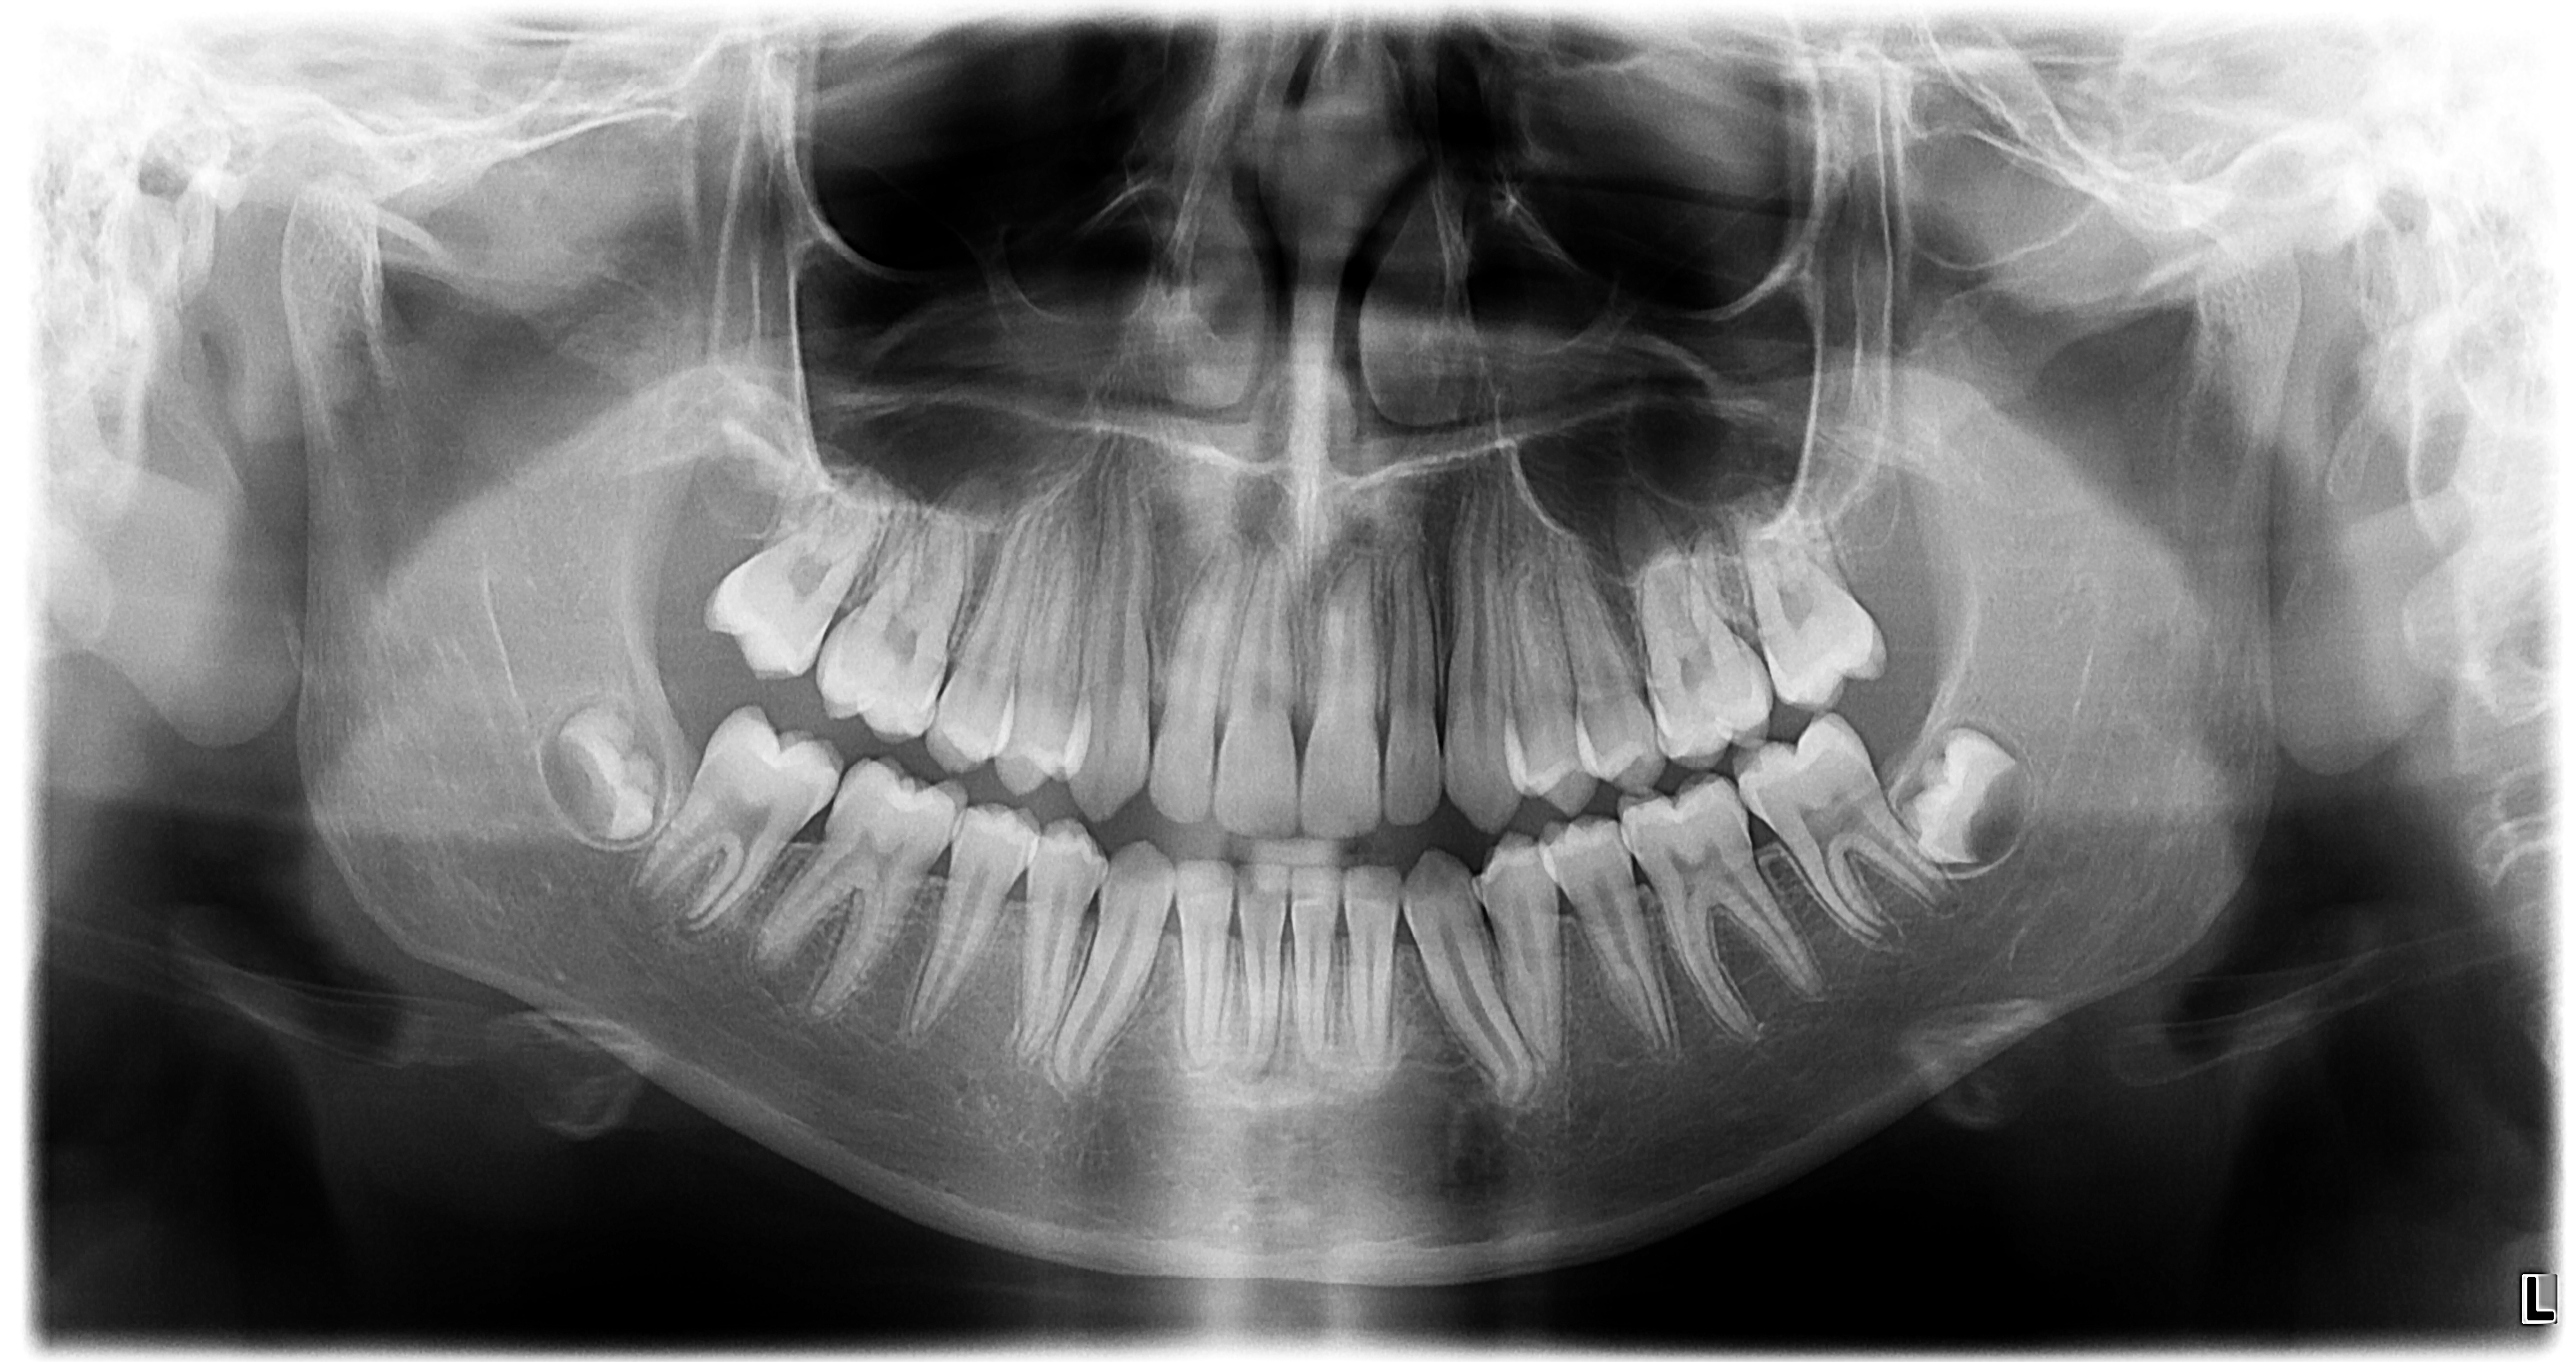

当院には正確で安全な治療を行うための検査機器をとして、最新鋭の歯科用CTシステムを導入しております。このシステムは、低い被ばく線量(総合病院などの医科用CTの1/10以下)で、3次元データの情報を得ることができ、これまでのレントゲン検査の診断が難しかった部分の診断も行えます。これにより患者さんのへのわかりやすい説明と更なる治療成績の向上が見込めます。